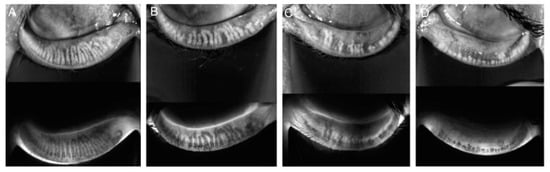

Meibography is a noninvasive imaging technique used to visualize the structure of the meibomian glands in vivo, providing valuable insights into glandular health and dysfunction. The system integrates a slit lamp equipped with an infrared (IR) transmitting filter and an IR charge-coupled device (CCD) video camera, allowing detailed imaging of the glands without the need for a transilluminating probe. This advanced setup enhances patient comfort and streamlines the assessment process. The evaluation of meibomian gland dropout, which refers to gland loss or structural alterations, was conducted by two trained assessors using a standardized meiboscore grading system. The meiboscore scale, ranging from 0 to 3, provides a consistent framework for quantifying glandular changes (Figure 1) [13,14].

The grading criteria are as follows:

• Grade 0 indicates no detectable gland loss.

• Grade 1 corresponds to gland loss involving less than one-third of the total glandular area.

• Grade 2 represents gland loss affecting between one-third and two-thirds of the gland area.

• Grade 3 denotes severe gland loss exceeding two-thirds of the total area [13].

Figure 1. Meiboscore for grades 0–3. Notes: (A) Grade 0 indicates no loss of glands. (B) Grade 1 corresponds to gland loss of less than 33%. (C) Grade 2 represents gland loss ranging from 33% to 66%. (D) Grade 3 signifies gland loss exceeding 66%.